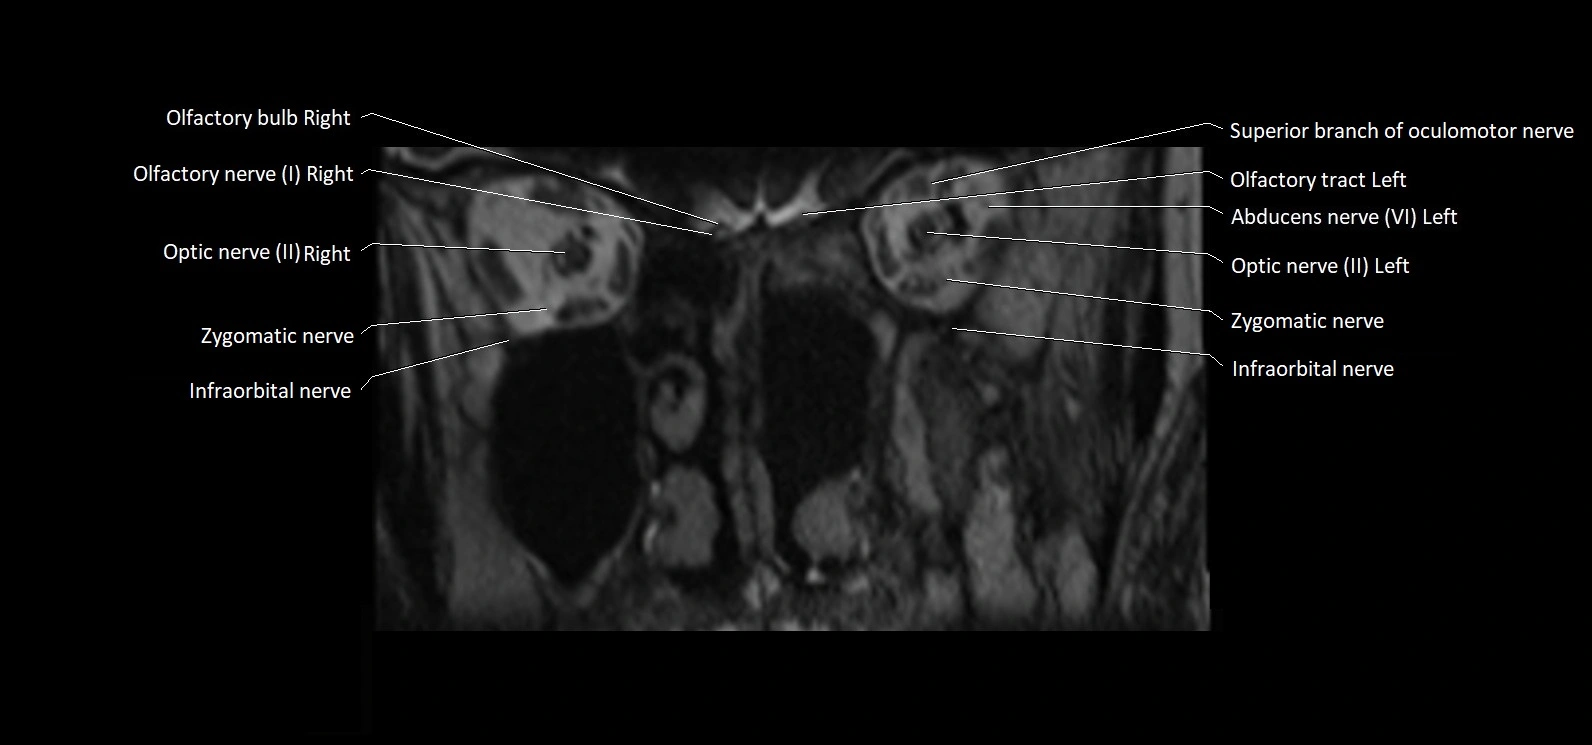

MRI Appearance

• The abducens nerve is a small, thin, linear structure

• Best visualized on high-resolution T2-weighted 3D MRI sequences (e.g., FIESTA or CISS)

• Seen as a hypointense (dark) line running from the brainstem at the pontomedullary junction, traversing the prepontine cistern, and entering Dorello’s canal under the petrosphenoidal ligament, then into the cavernous sinus, and finally the orbit

• May be challenging to visualize in standard MRI due to its small size

• Pathology may be inferred by absence, displacement, or enhancement of the nerve

MRI images

image